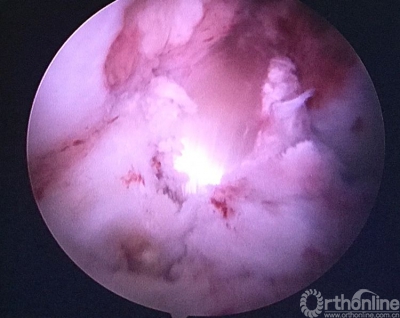

用由小到大的空心钻头钻股骨隧道,观察隧道情况,至8mm时隧道内骨面90%达新鲜化。

股骨隧道内取出的原重建肌腱及袢,糜烂。

己经完成的股骨隧道,改用强生横穿钉固定。